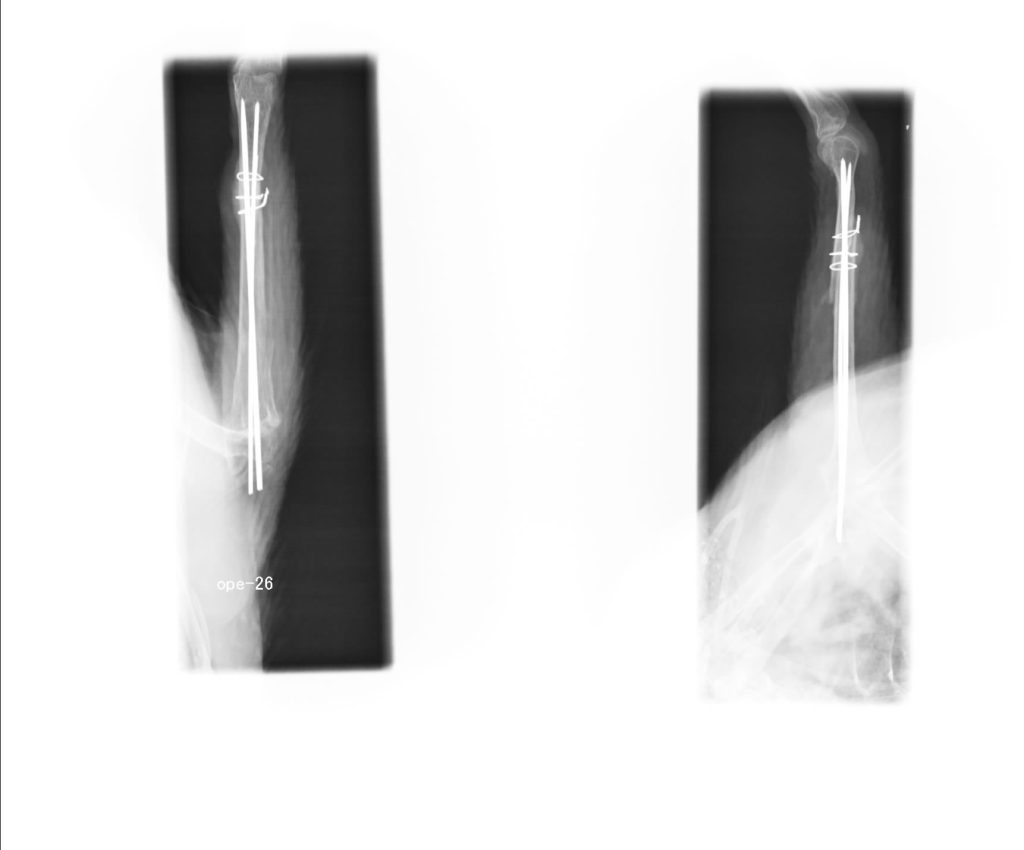

骨折などはピンを入れたりしていますが、

ピン入れて骨折治癒烏骨鶏

フクロウも骨折